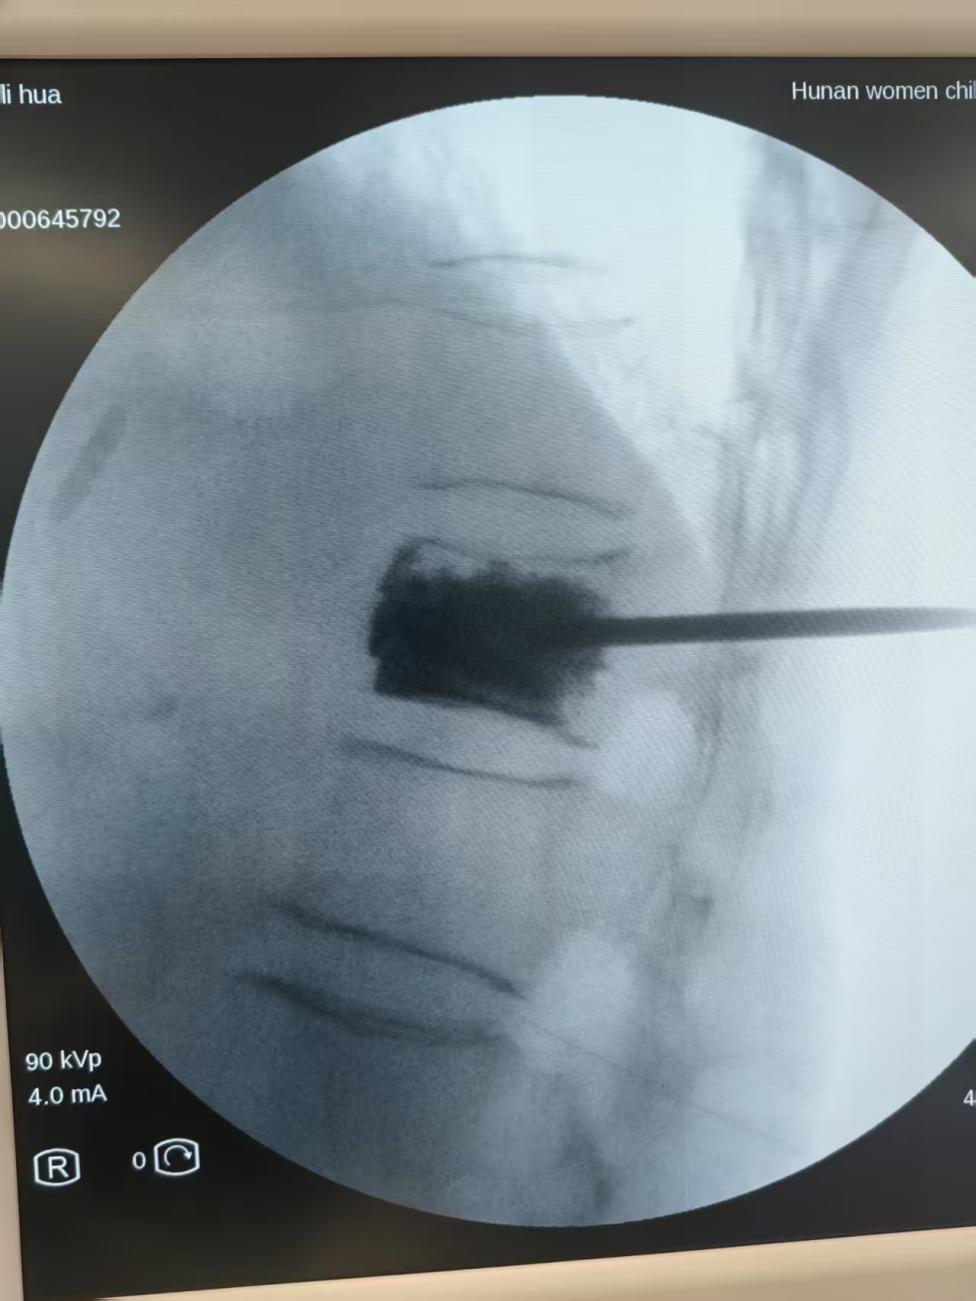

经影像学检查,确诊为胸 11 椎体压缩性骨折,压缩程度达 50% 以上。考虑到患者高龄合并严重骨质疏松,传统开放手术风险较高,脊柱外科团队决定采用经皮椎体后凸成形术(PKP)进行微创治疗。

湖南妇女儿童医院骨科副主任康长周用生活化比喻解释:"就像修补塌陷的墙体,我们用特制'骨水泥'通过细针注入伤椎,20 分钟就能凝固成型。这种微创技术: 创口仅 3 mm(约圆珠笔尖大小)、手术全程清醒无痛。」

入科后 4 小时,在放射和手术室的密切配合下,骨科团队仅用时 30 分钟便成功完成手术。出血量仅 2 ml,只有皮下穿刺针微量出血。术后, 患者疼痛明显缓解。